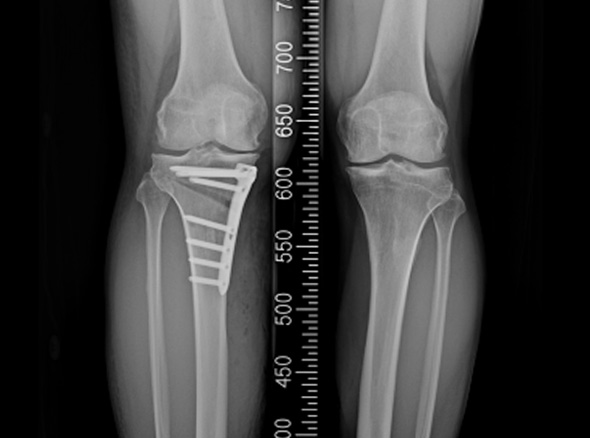

* 환자에게 받은 소중한 자료입니다.

※ 금속판과 나사는 수술 후 약 1~2년 후 제거합니다.

관절내시경을 이용하여 연골재생이나 연골판에 필요한 치료를 시행한 후 경골(무릎 아래 뼈)의 근위부의

계획한 위치까지 절골을 시행한 후 뼈의 탄성을 이용하여 벌립니다. 그리고 금속판과 나사로 고정하여

수술 전 계획했던 X자형 또는 1자형 다리를 만들고 빈 공간에 뼈를 이식하여 골유합을 유도합니다.